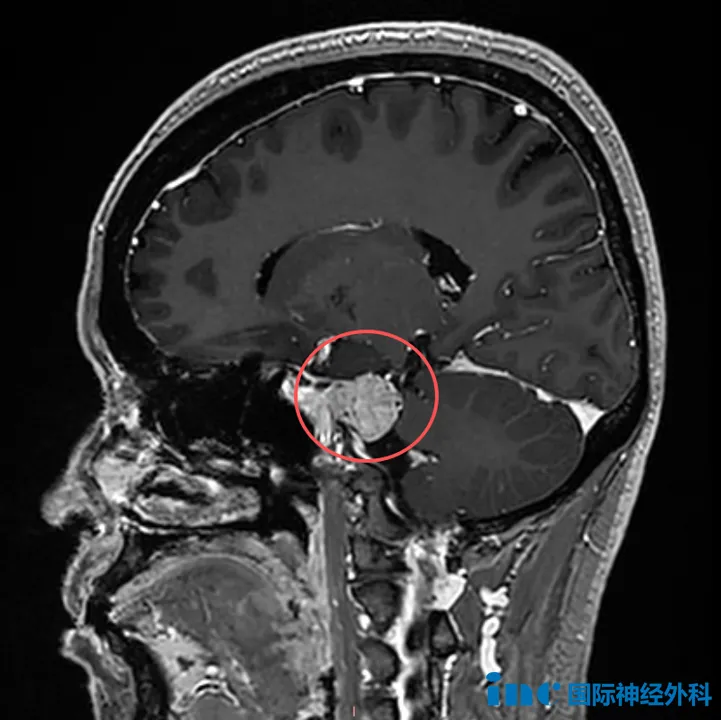

脑膜瘤是中枢神经系统肿瘤中,最具有特征性影像学表现的肿瘤。在X线和脑室造影的年代,检查结果仅起到提示作用。现在,影像学技术可以对脑膜瘤进行无创、准确地诊断,明确病灶与周围...

岩斜区位于颞骨岩部背面与枕骨斜坡部的岩斜裂汇合处,从岩骨尖至颈静脉孔。内侧至斜坡中线,外侧至第Ⅴ、Ⅶ和Ⅷ脑神经,上缘为鞍背,下缘为颈静脉孔水平;下方为枕骨大孔区。岩斜区脑...